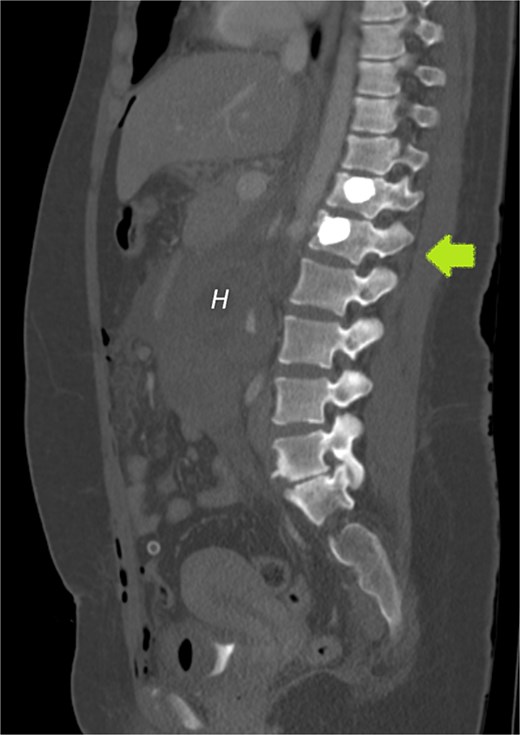

Sagittal plane CECT shows the hematoma (H) displacing the pancreas ventrally, proving its retroperitoneal location. Active bleeding is seen adjacent to the gestational sac (arrow). A normal appearing, nonpregnant uterus is also visible.

Our patient had an uneventful vaginal delivery, no abortions, no curettages, or tubal sterility. The patient’s only relevant history was of abdominal trauma during a traffic accident. A study by Cigerci et al found abdominal injuries to be present in as many as 23% of patients with traumatic thoracolumbar fractures [12]. The position of the gestational sac is just below the level of the fractured L1 vertebra (Fig. 7) could suggest an association of RPEP with previous abdominal trauma.

CECT of the abdomen and pelvis in the sagittal plane, bone window. Gestational sac (H for hematoma) was implanted just inferior to the level of a previous traumatic L1 vertebral fracture (arrow).